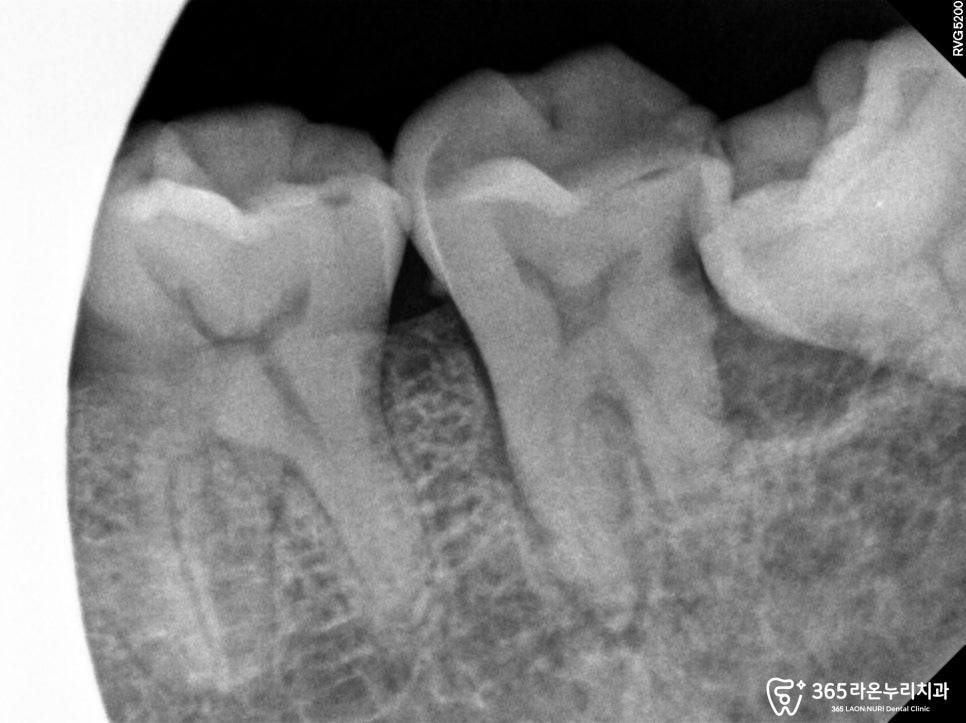

큐레이와, 치근단 사진을 함께보면

주위로 골파괴 현상도 같이 관찰이 됩니다.

손으로 살짝 건들여도, 동요도가 있는 상태였기에

문제가 있었습니다.